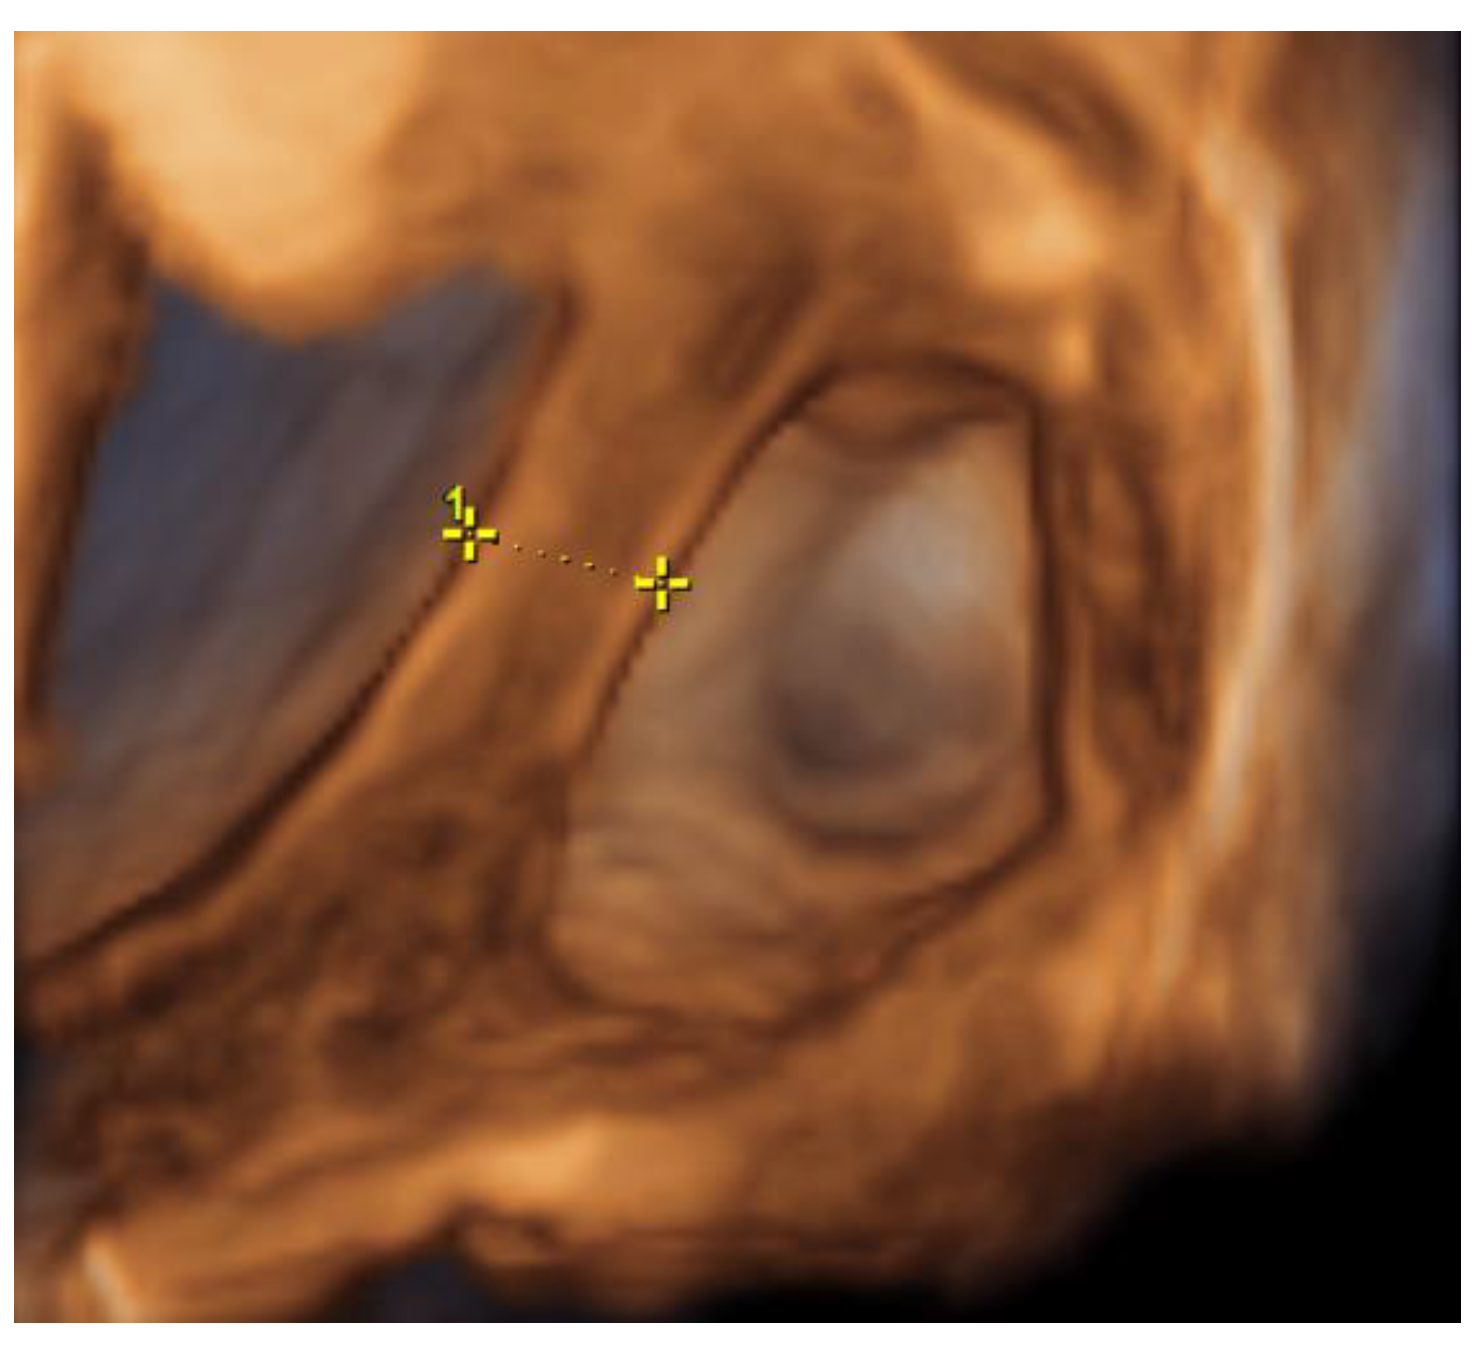

Figure 3. Left cornu of the uterus, observed during diagnostic laparoscopy.

Medicina 57 01207 g003

Figure 4. Left cornu of the uterus, observed during diagnostic laparoscopy.

During hospitalization, blood and urine tests’ results were within the normal range. A multidisciplinary team (MDT) decided to keep monitoring the growth of both pregnancies by ultrasound while maternal vitals were stable and noted that further management would be determined according to the clinical situation. On the third day of hospitalization the patient started to feel more severe pain in the hypogastric region, radiating to the back and the left groin. The MDT made a decision to perform a diagnostic laparoscopy. Laparoscopy confirmed heterotopic angular pregnancy in the left enlarged, swollen cornu of the uterus. The left ovary and fallopian tube were not damaged and there were no signs of uterine rupture. Figure 3 and Figure 4.